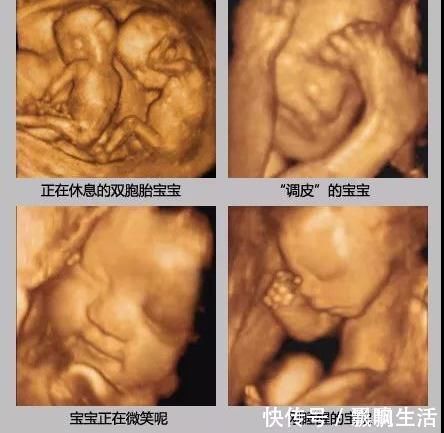

四维彩超,大多是排畸时做,看得会更清楚些,而且还会把当时拍到的胎儿样子,定格下来作为纪念。

于是就可能看到胎宝宝各种“状态”,有的很淘气,各种“做鬼脸”不配合,但也有的比较听话,能很快的顺利做完。

检查时胎儿的“表现”,也可以作为出生后性格的参考,在肚子里就爱搞怪的宝宝,出生后也大多比较淘气。